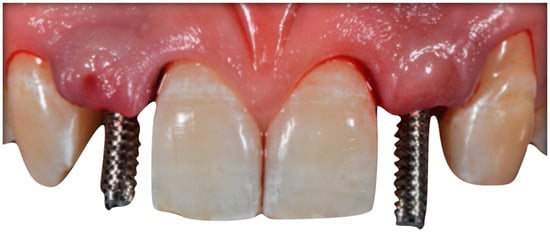

The case describes rehabilitating two congenitally missing lateral incisors in a young patient (38 years old) undergoing orthodontic treatment to create the necessary space for implant placement (Figure 1 and Figure 2). Two fibre-reinforced composite Maryland bridges (Tender Fiber Quattro—Micerium) were utilised for provisional rehabilitation (Figure 3, Figure 4 and Figure 5). Two Osstem TSIII 3.5 × 10.0 implants (1.5 mm subcrestal), two straight Osstem Zirconia abutments, and two-layered lithium disilicate crowns were employed for the definitive restoration (Figure 5, Figure 6, Figure 7, Figure 8, Figure 9, Figure 10, Figure 11, Figure 12, Figure 13, Figure 14, Figure 15, Figure 16, Figure 17, Figure 18, Figure 19 and Figure 20) [,]. The dental implant position was planned after a three-dimensional radiographic analysis in a prosthetically guided way. Patient rehabilitation was performed with an immediate post-surgery provisional (Maryland-type, cemented with a resinous cement) application. Subsequently, a delayed loading of the new provisional dental implant was retained (cemented with zinc oxide eugenol cement) and finally, definitive crowns (cemented with a definitive resinous cement) on Osstem® abutments were installed (3 months).

Figure 7. Implant placement (Osstem TSIII 3.5 × 10).

Figure 9. Transfer of implant position to the laboratory: Placement of Ti temporary abutments (a); Fixation of work in the transfer key using pattern resin, drilling on the master hard stone model, and focus of analogues in the model by recasting hard stone (b).